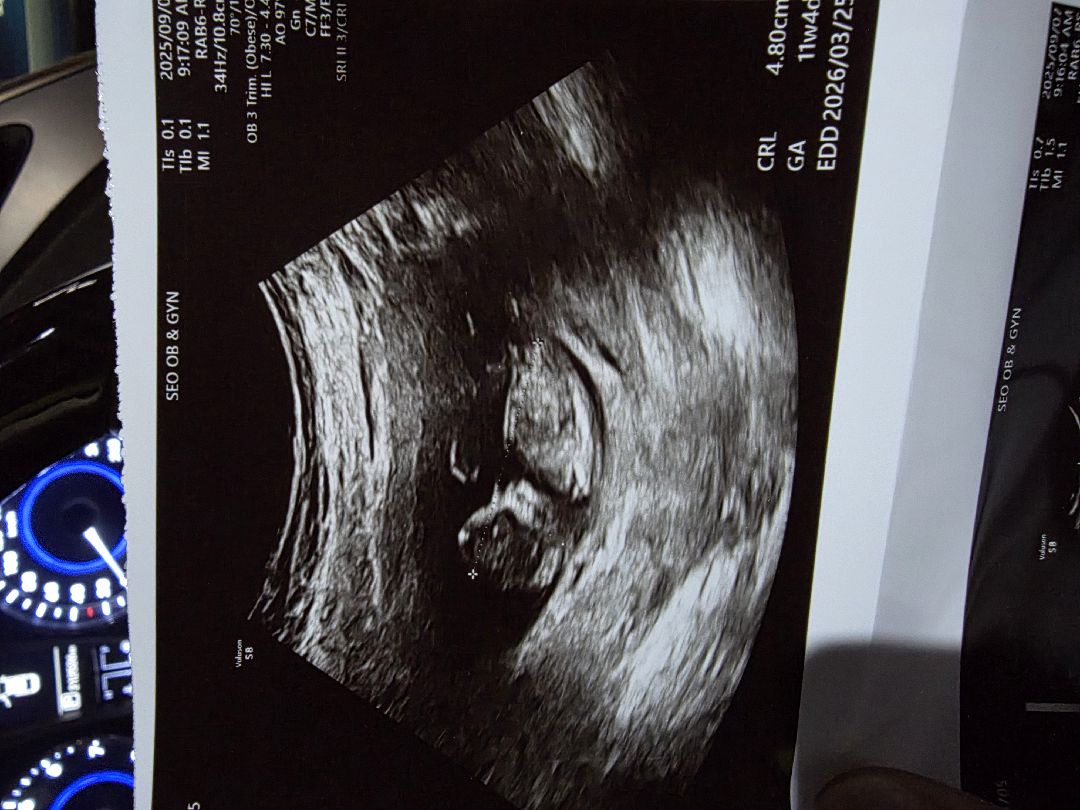

11주 각도법 봐주세요

오늘보고왔는데 성별에 연연하지않고 건강하게만 나오거라했는데 오늘부쩍 큰모습을보니 궁금하기도하네요ㅎㅎ